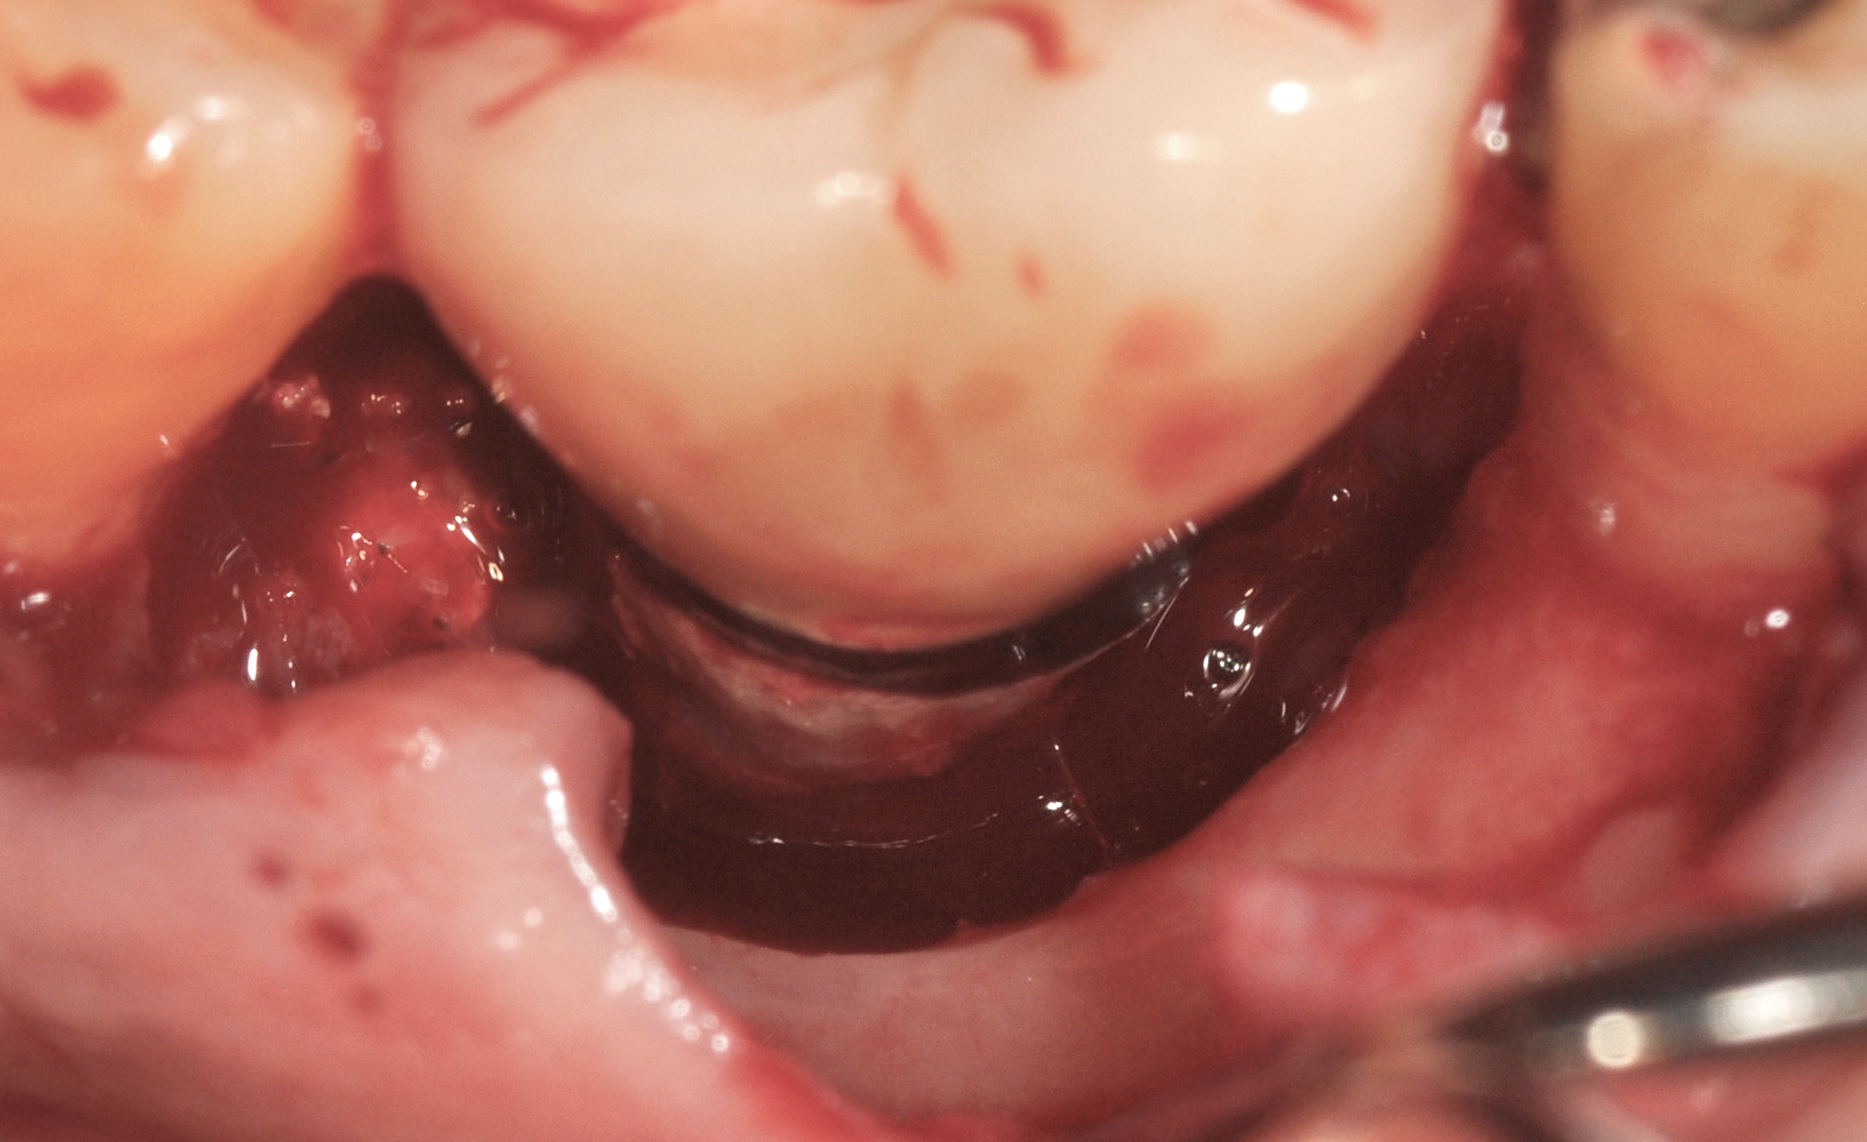

A surgical flap procedure was performed with the intent of thoroughly debriding the granulomatous tissue from the osseous defect (Figure 18 and Figure 19), mechanically and chemically detoxifying the surface of the implant (Figure 20 through Figure 22), and grafting the infrabony component of lesion with bone xenograft (Bio-Oss®, Geistlich Pharma, www.geistlich-na.com) in an attempt to reduce the vertical defect (Figure 23). To concurrently resolve the mucogingival problem, the plan called for placing a dermal allograft (Dermis Allograft, DENTSPLY International, www.dentsply.com) on the buccal (Figure 24) and then replacing the flap (Figure 25).

Fig 23. Fill of the infrabony defect with bone xenograft.

Fig 24. The bone graft was covered with dermis allograft that will act as a barrier to prevent epithelial downgrowth while simultaneously augmenting the vestibule and thin marginal gingiva that were contributing to the mucogingival problem.